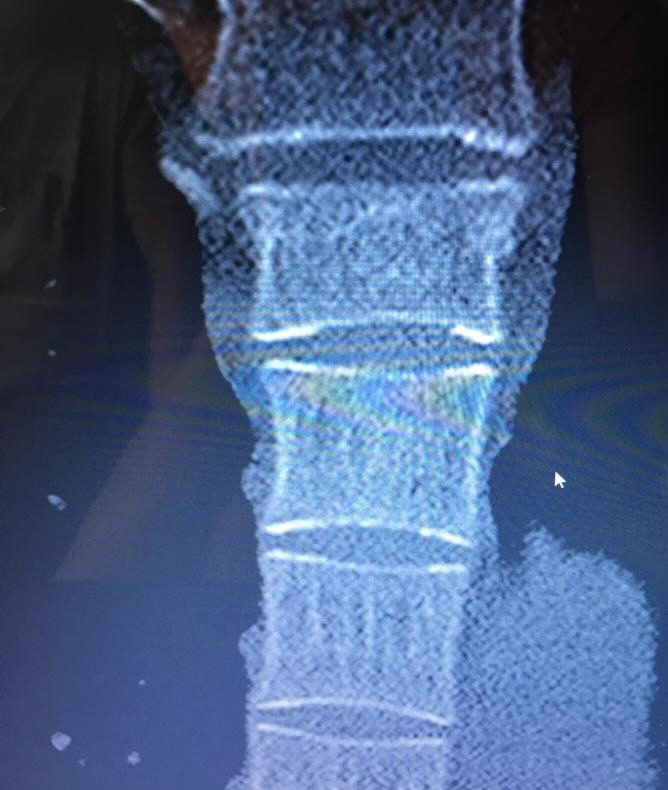

Ein 48-jähriger Patient leidet seit sechs Monaten an chronischen thorakalen Rückenschmerzen mit Ausstrahlung in die rechte Schulter nach einer BWK4- Deckplattenkompressionsfraktur, die er sich bei einem Mountainbikesturz zugezogen hatte. Die Fraktur wurde zunächst konservativ mit Schmerzmitteln nach WHO-Schema behandelt. Nach sechs Wochen konnte er bei stabiler Knochensituation und erfolgter MRT-Kontrolle mit Physiotherapie beginnen und wieder eingeschränkt in den beruflichen Alltag eingegliedert werden. Stoß- und Sprungbelastungen wurden für zwölf Wochen gemieden. Nach sechs Monaten plagten ihn immer noch anhaltende, mittlerweile chronische Rückenschmerzen, die zudem nun in die rechte Schulter ausstrahlten. Ein sensomotorisches Defizit wurde verneint. Er hatte einen hohen Leidensdruck, nachdem er selbst im normalen Alltag Schmerzen auf einer visuellen Analogskala von 7/10 angab und seiner Leidenschaft – dem Radfahren – nicht mehr nachgehen konnte. Wegen unerwünschter Nebenwirkungen hatte der Patient seine Schmerzmedikation mit Ibuprofen und Tilidin retard bereits nach drei Monaten beendet.